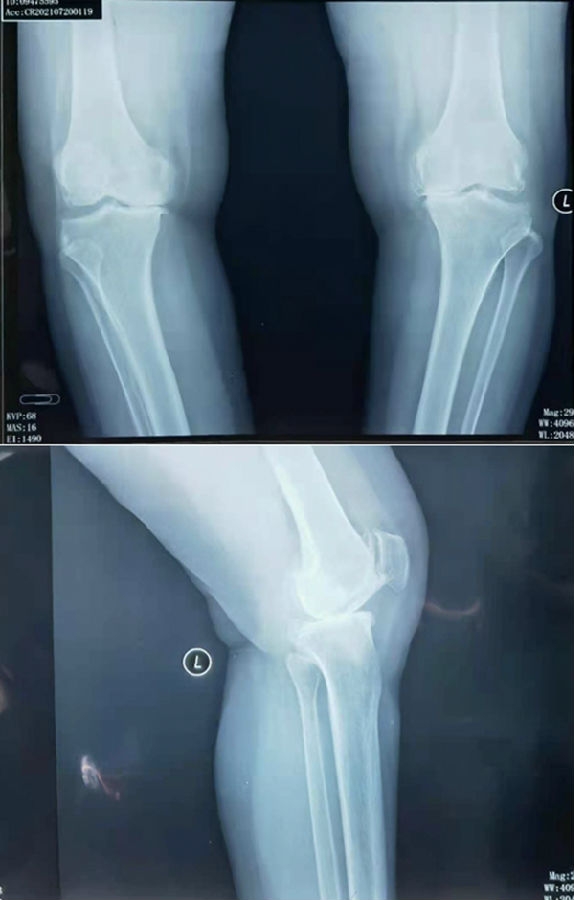

患者女,65岁,通过负重正侧位片,诊断:前内侧骨关节炎,符合单髁置换指征。术中发现外侧小片软骨剥脱。但是,术前屈曲二十度外翻应力位,外侧关节间隙完好,仍按计划行单髁置换术。

术前影像